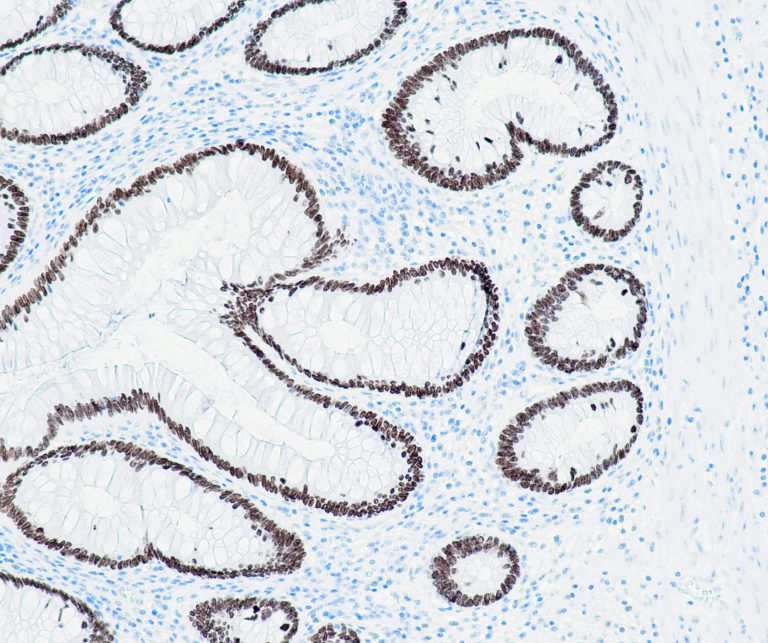

Gastrointestinal (GI) Pathology